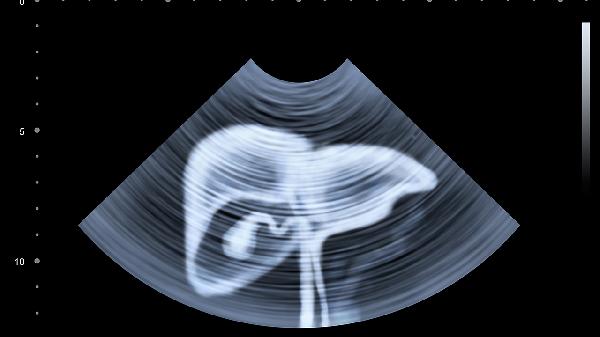

土三七中的吡咯里西啶生物碱可损伤肝窦内皮细胞,引发肝小静脉闭塞症。表现为肝肿大、腹水等症状,影像学检查可见特征性"地图样"肝实质改变。